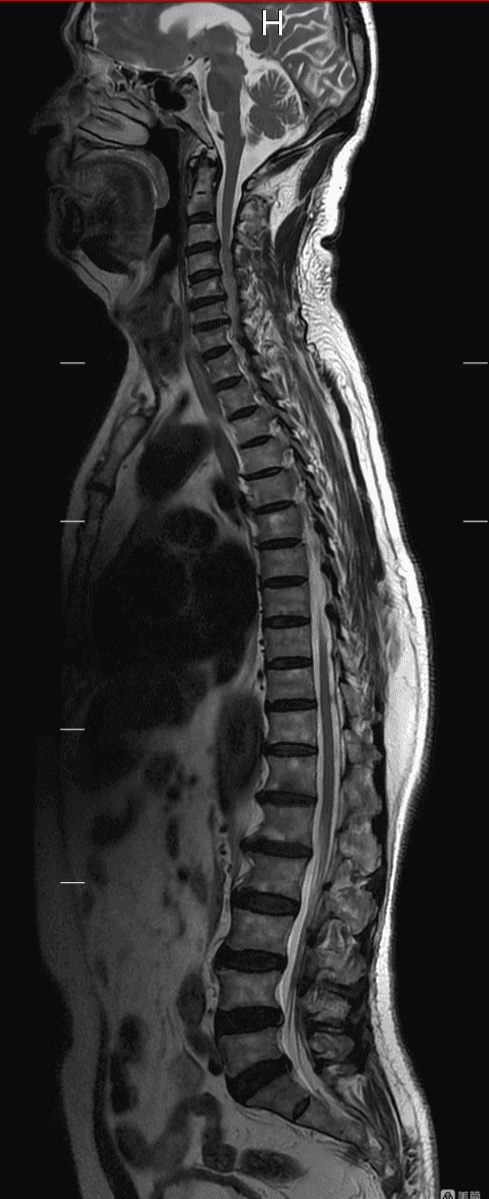

全脊柱磁共振成像是近年来发展起来的新技术,对一种病变治疗/检查手段,全脊柱成像是一次定位利用检查床移动患者不动完成全脊柱的扫描,避免了多次搬动患者的不便,特别是多节段脊柱损失缩短了检查时间,提高了图像质量。通过图像拼接后处理技术。可以在一幅图像上显示颈、胸、腰、骶尾椎完整的脊柱图像,俗称脊柱全长。在矢状面上可以形象直观、清晰完整的显示椎管内、全段脊髓、脊柱及周围韧带连续的磁共振图像。

上图为我院患者全脊柱磁共振成像图